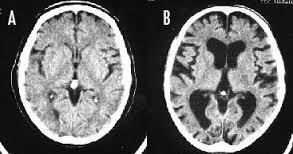

>>592 喫煙をすると、頭が悪くなるのは本当です。 長期の喫煙により、大脳皮質が薄くなり、認知機能が低下してしまうのです。 画像左(A)は正常な脳、右(B)は喫煙者の脳です。 正常な脳と比べて、喫煙者の脳は、萎縮して隙間だらけになってしまっています。 喫煙をやめても、元の状態に回復するまで、数十年はかかるそうです。

--- 「喫煙者の脳」やはり異変が起きていた(石田雅彦) - Yahoo!ニュース ---

タバコを吸うと脳がすっきりするのは真っ赤な嘘だ。研究によれば喫煙者の脳では明らかに異常が起きている。認知機能も低下し、大脳皮質が元に戻るのには25年もかかる。一刻も早くタバコなど止めたほうがいい。